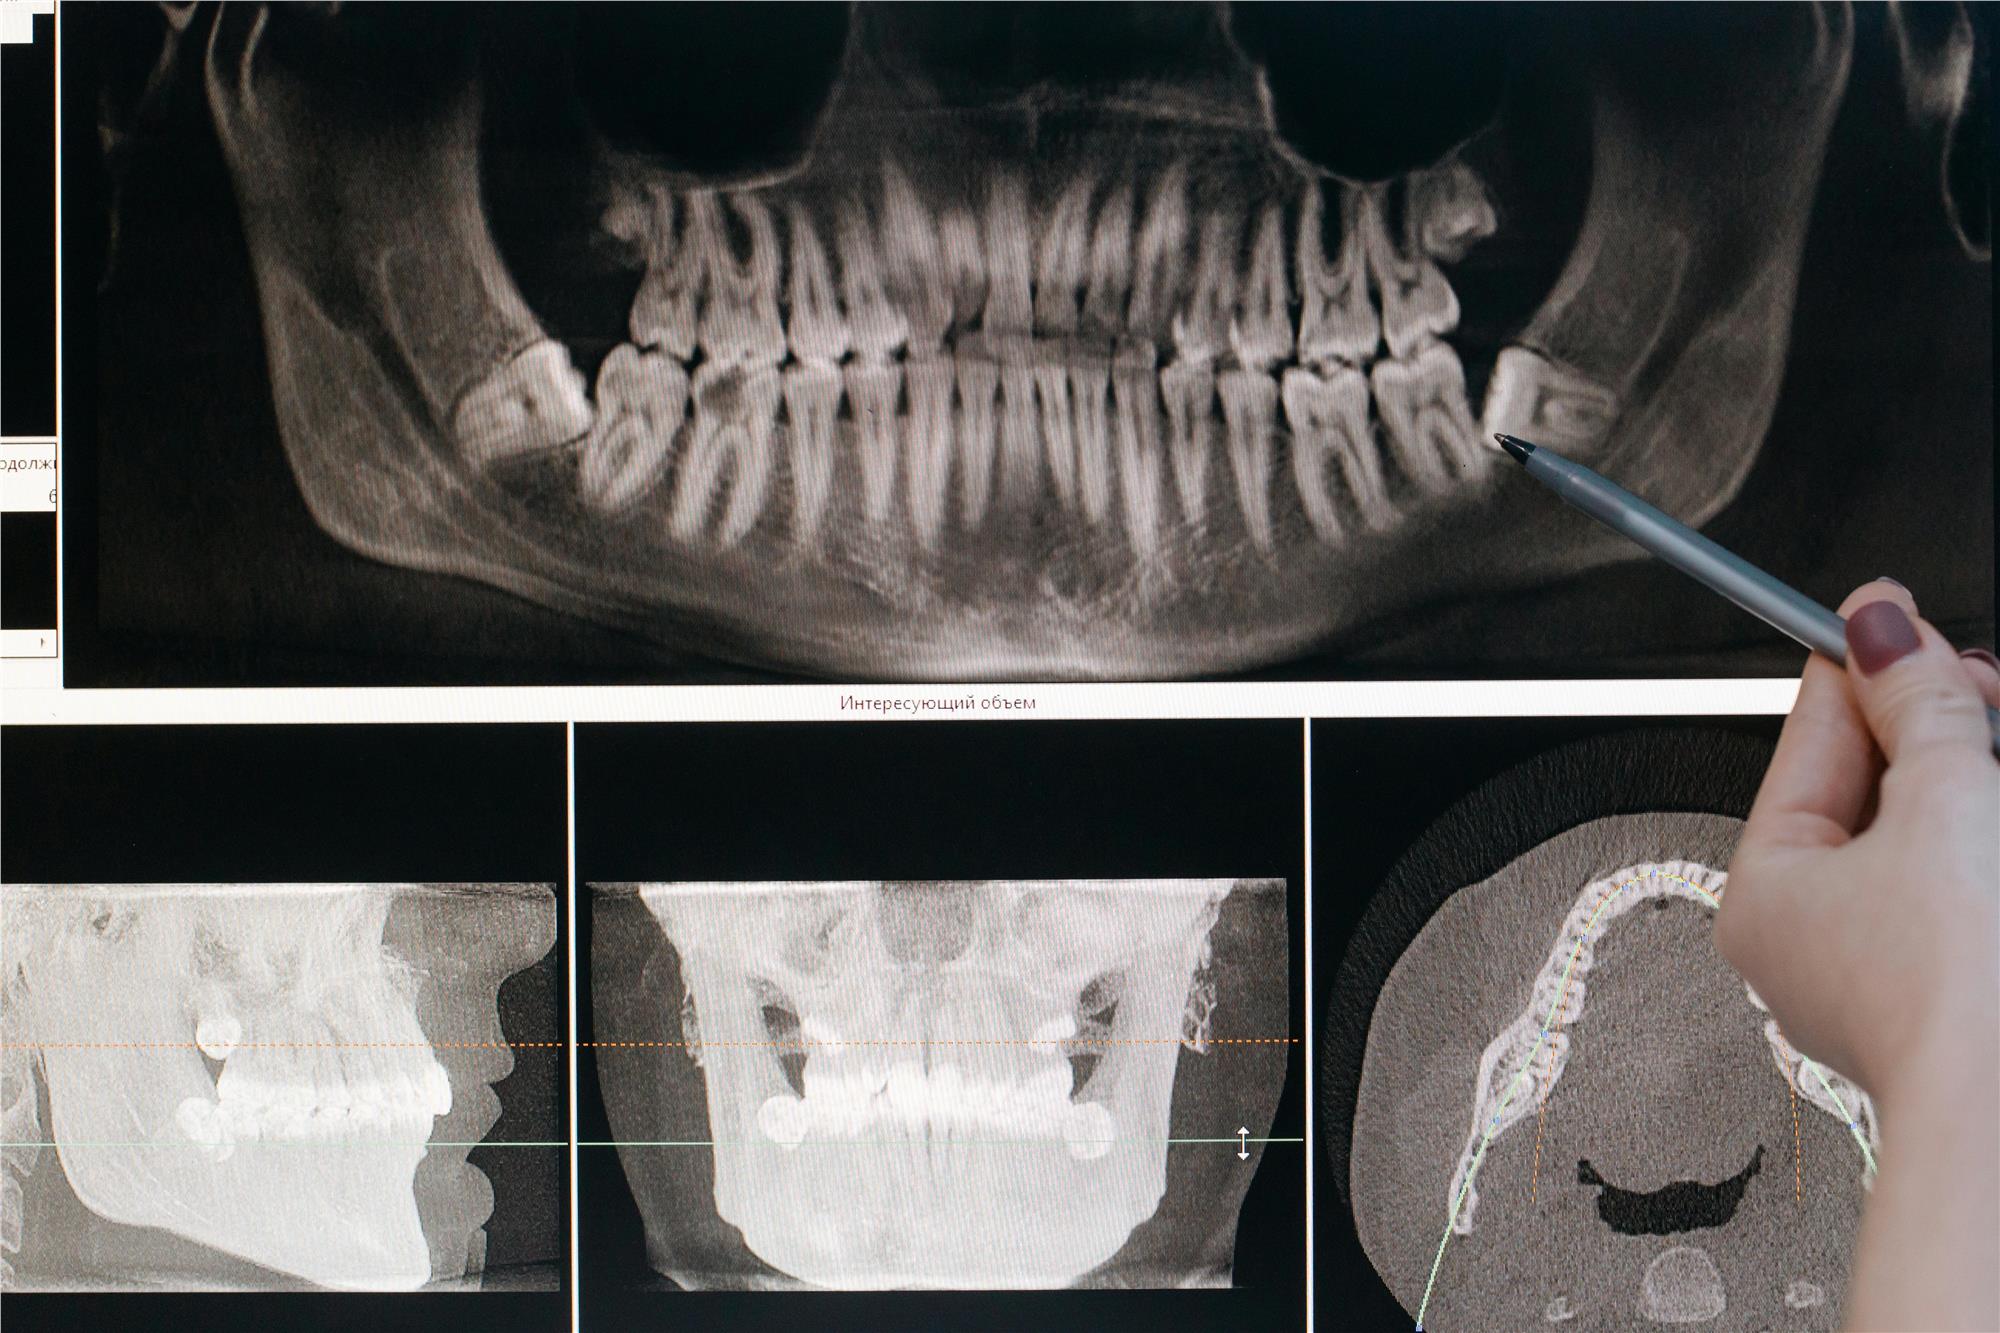

Dental X-rays

Dental x-rays can help your dentist detect oral health problems, especially problems such as cavities and gum disease, before they get worse. There are many different types of dental x-rays, including intraoral and extraoral. Dental x-rays are an important tool for proper oral health and care.